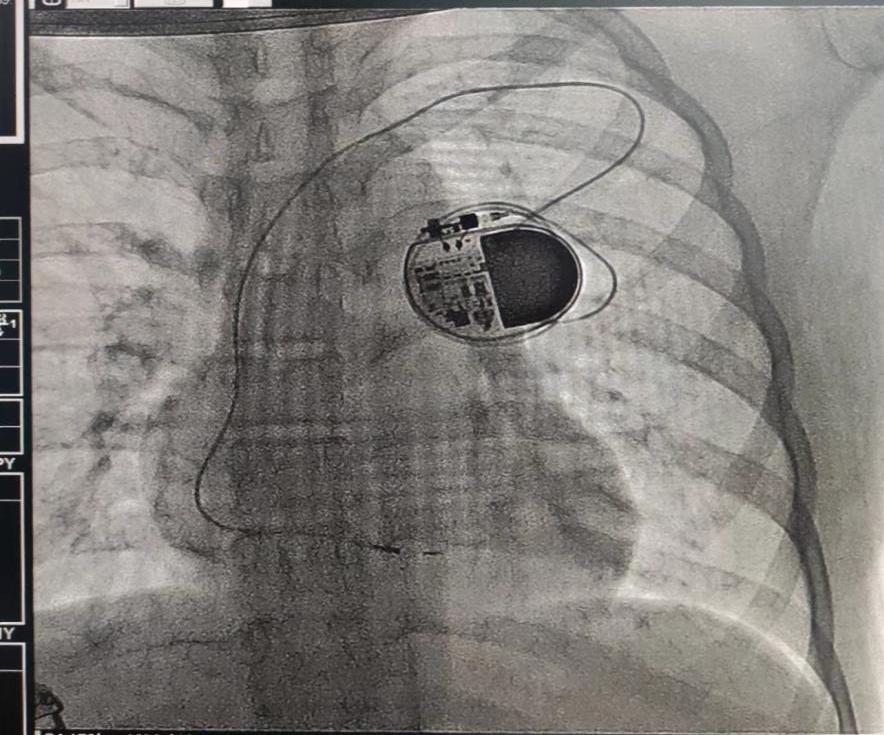

蓄上电,获“心”生,捷克论坛 为12岁女孩再次成功植入心脏起搏器

小雨不到半岁时,就被诊断为先天性的三度房室传导阻滞。于是,满3岁那年,小雨在捷克论坛 进行了人工心脏起搏器植入术。在起搏器的“罩”护下,小雨安全健康的成长着。今年713日,起搏器程控显示小雨的起搏器电池寿命不到1个月,必须尽快更换起搏器。考虑到小雨才12岁且需要终身起搏,需要多次更换、升级起搏器,接诊的张翼主任医师团队综合评估小雨初始植入时年龄、体重、原发疾病等因素及生长发育特点,制定个体化、精细化的起搏器更换方案并于718日为小雨行起搏器更换术。术后3天,小雨开心的出院了,新的起搏器将又为她续上新的征程。727日,小雨来院复查,各项指标均正常。